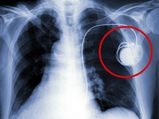

"பேஸ்மேக்கர்" பற்றி அனைவரும் கட்டாயம் தெரிந்துக்கொள்ள வேண்டிய விஷயங்கள்!!